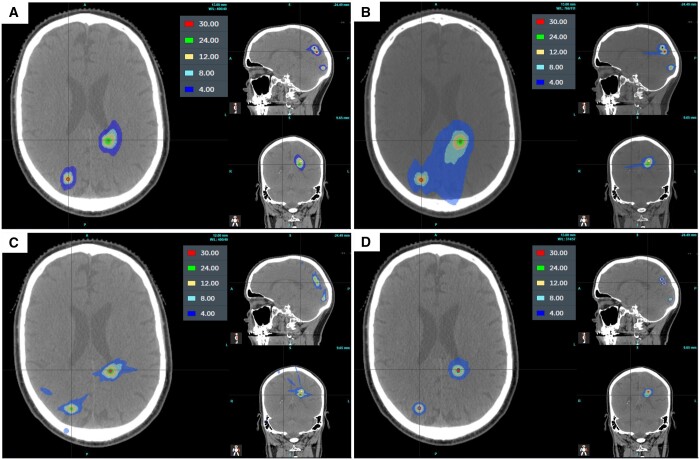

Objectives: This study compared plans of high definition (HD), 2.5 mm width multi-leaf collimator (MLC), to standard, 5 mm width, isocentric linear accelerator (linacs), CyberKnife (CK), and Gamma Knife (GK) for stereotactic radiosurgery (SRS) techniques on multiple brain metastases.

Methods: Eleven patients undergoing SRS for multiple brain metastases were chosen. Targets and organs at risk (OARs) were delineated and optimized SRS plans were generated and compared.

Results: The linacs delivered similar conformity index (CI) values, but the gradient index (GI) for HD MLCs was significantly lower (P-value <.001). Half the OARs received significantly lower dose using HD MLCs. CK delivered a significantly lower CI than HD MLC linac (P-value <.001), but a significantly higher GI (P-value <.001). CI was significantly improved with the HD MLC linac compared to GK (P-value = 4.591 × 10-3), however, GK delivered a significantly lower GI (P-value <.001). OAR dose sparing was similar for the HD MLC TL, CK, and GK.

Conclusions: Comparing linacs for SRS, the preferred choice is HD MLCs. Similar results were achieved with the HD MLC linac, CK, or GK, with each delivering significant improvements in different aspects of plan quality.

Advances in knowledge: This article is the first to compare HD and standard width MLC linac plans using a combination of single isocentre volumetric modulated arc therapy and multi-isocentric dynamic conformal arc plans as required, which is a more clinically relevant assessment. Furthermore, it compares these plans with CK and GK, assessing the relative merits of each technique.